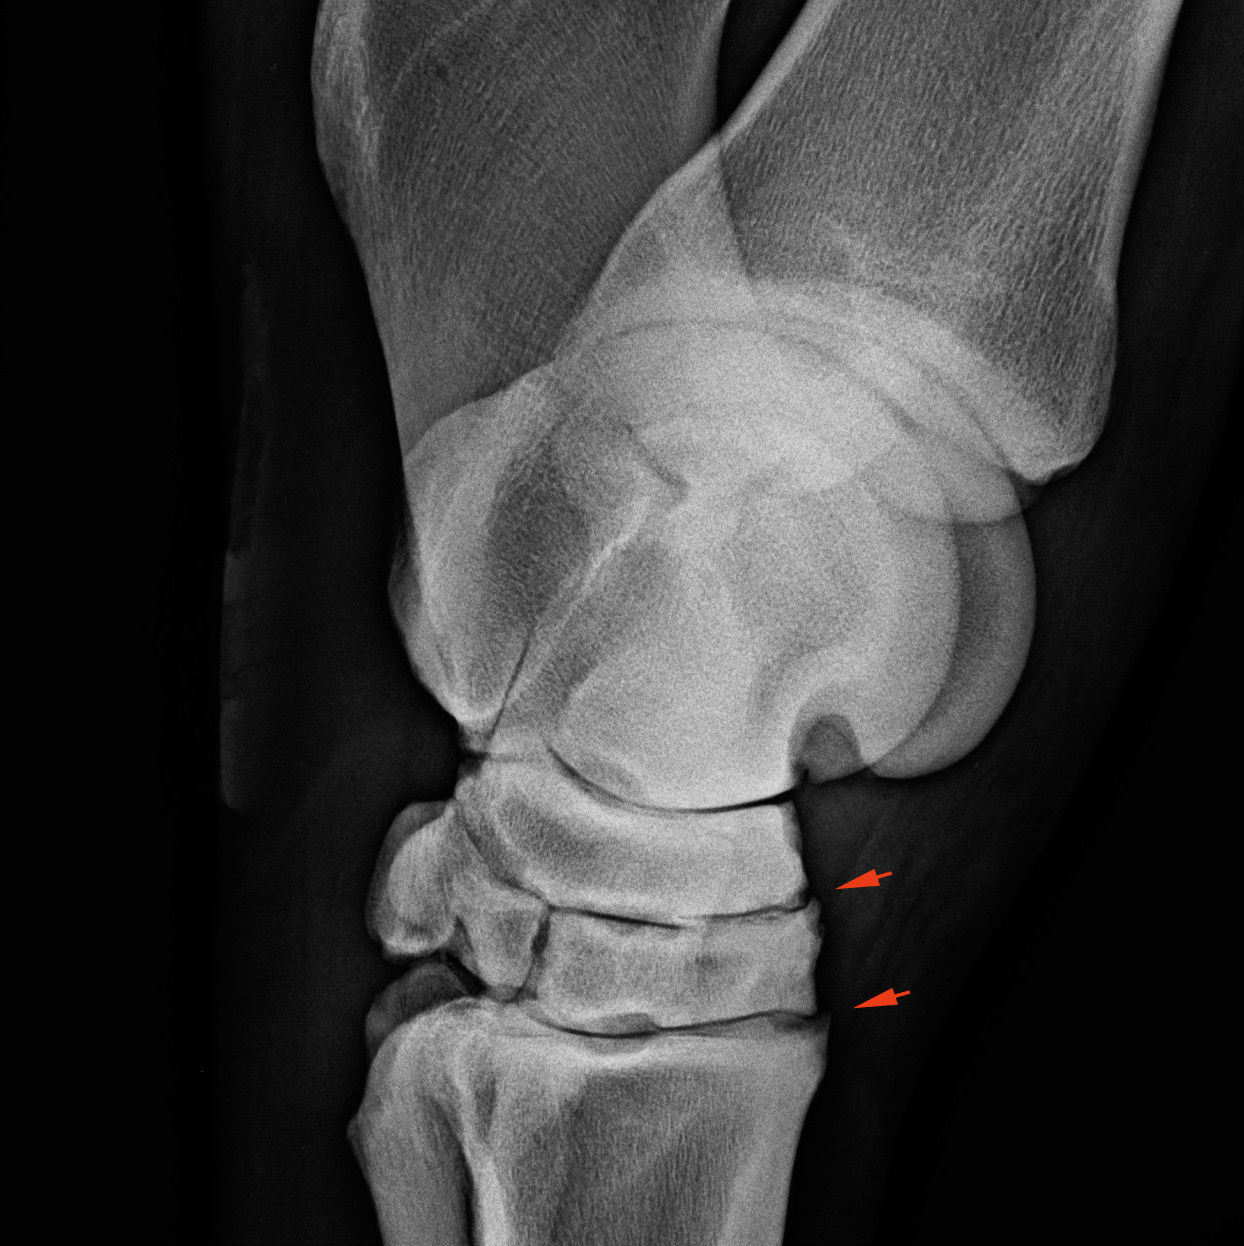

Kezdeti elváltozások. A nyilak az ízületek szerkezetének felbomlását, csontfelrakódások képződését mutatja.